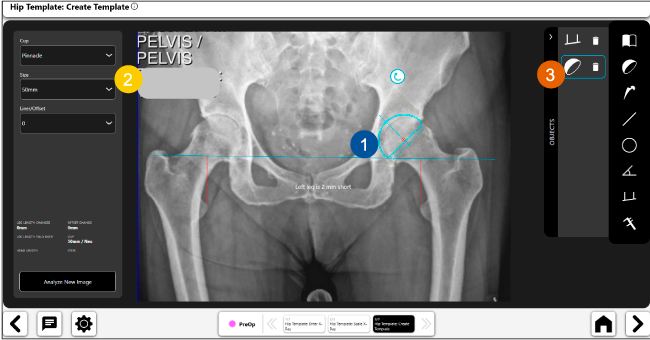

Planeación preoperatoria mediante la creación de plantillas digitales para reemplazo de cadera y análisis intraoperatorio

Beneficios de la planeación preoperatoria con Velys Hip Navigation ™

Disponibilidad de plantillas digitales de cadera.

Expediente histórico y personalizado, optimiza la planeación con el calendario de casos realizados en Velys TM y utiliza los íconos interactivos para una rápida revisión.

Espacio colaborativo: puede compartir los casos entre cirujanos y sus equipos mediante la funcionalidad de intercambio de información.

Anotaciones digitales y herramientas de análisis de longitud de pierna.

Con tecnología ONETRIAL® que calcula automáticamente el cambio en la longitud de la pierna y el desplazamiento para todas las combinaciones de implantes en una tabla fácil de leer.